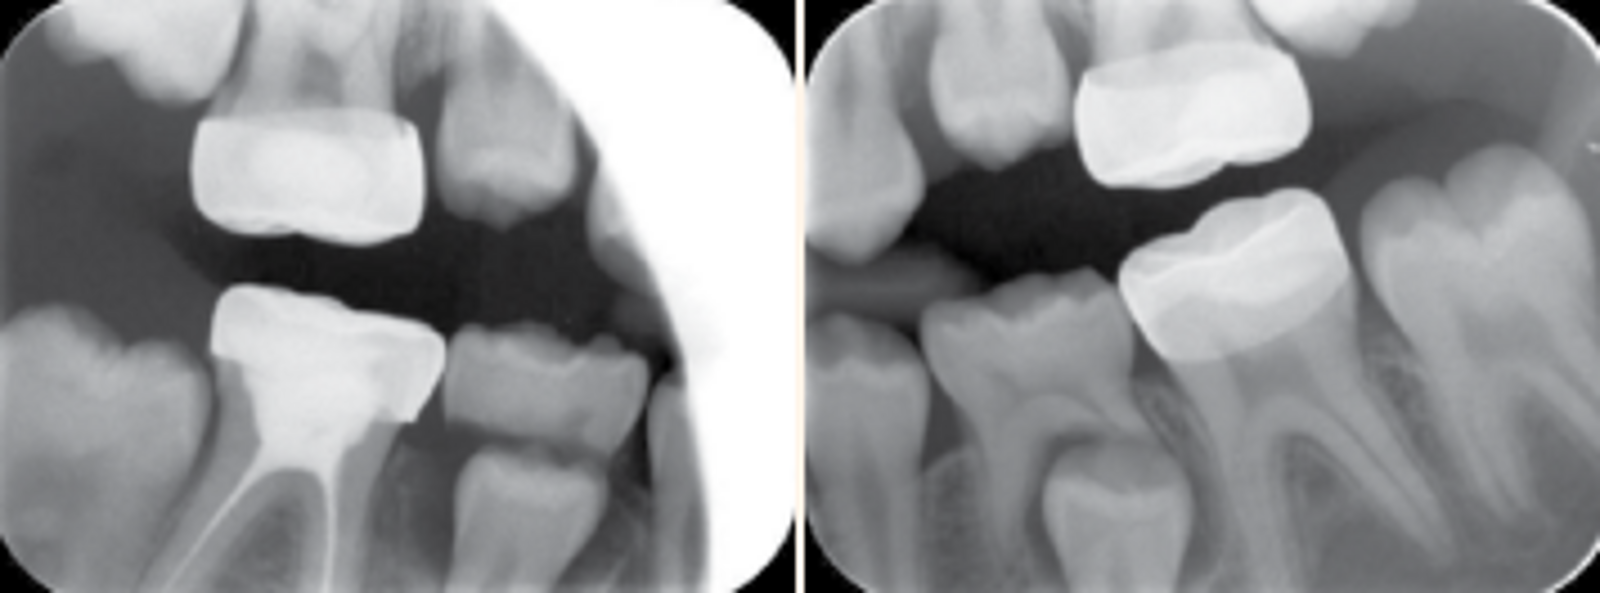

As S.S’s is considered to be of high caries risk status .She was kept on regular recall programme including recall visits and fluoride varnish application every 3 months, radiographs every 6 months. See Figures 3 (a, b, c, d & e).

Fig. 4 (a & b). Bitewing radiographs taken 6 months post treatment completion .Radiographic finding, fully seated crowns of all first permant molars with no progression of any pathological lesion underneath the SSC.